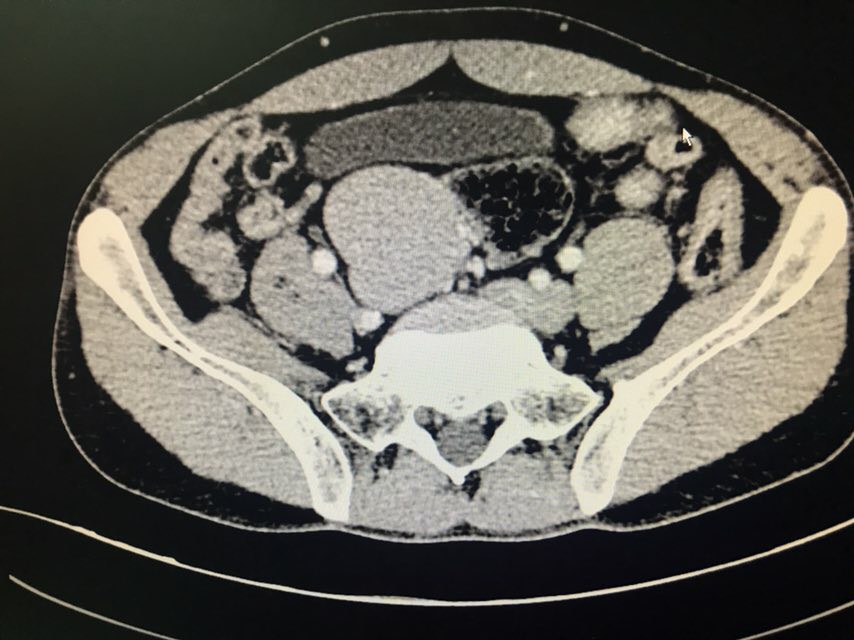

患者男性,43岁。主诉:发现盆腔占位1+月。现病史:患者1+月前于当地医院体检发现盆腔包块,于2018-08-28我院行泌尿系超声示:右侧髂窝实性占位伴钙化;2018-08-31我院行CT下腹部盆腔增强扫描示:下腹部及盆腔内多个软组织结节肿块影,肝右后叶上段囊肿;2018-09-07我院行病理检查示:盆腔肿瘤,倾向神经内分泌肿瘤,需行免疫组化染色检查;2018-09-07我院行膀胱超声示:超声引导下膀胱右侧盆腔内实性团块CNB。现患者为求手术治疗,于我院门诊就诊,以“盆腔肿瘤”收入我科。既往史无特殊。

查体:双侧腰部外形对称,皮肤无红肿,双肾区无叩痛,双肾下极未扪及,双输尿管行程区无压痛,膀胱区无隆起及压痛。双侧腹股沟区未扪及异常,无压痛;阴囊及尿道口未查。辅助检查:泌尿系超声(2018-08-28本院):右侧髂窝实性占位伴钙化;CT下腹部盆腔增强扫描(2018-08-31本院):下腹部及盆腔内多个软组织结节肿块影,肝右后叶上段囊肿;病理检查(2018-09-07本院):盆腔肿瘤,倾向神经内分泌肿瘤,需行免疫组化染色检查;膀胱超声(2018-09-07本院):超声引导下膀胱右侧盆腔内实性团块CNB。